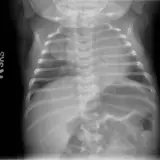

Over 2,100 interactive radiology cases, curated by radiologists for your level of training. Scroll, window, and view cases full screen — just like on PACS. Click linked findings in each writeup to jump straight to them on the image. Cases include sample reports, a focused discussion section, original illustrations, and videos.

Casos totalmente interactivos con las herramientas que esperaría de un PACS: scroll, ventana, zoom, pan, mediciones, ROI y modo de pantalla completa.

• Anotaciones enlazadas

Anotaciones extensas resaltan los hallazgos clave directamente sobre los casos. Haga clic en los hallazgos enlazados dentro de la descripción del caso para saltar a su ubicación exacta en el estudio.

Aprenda con eficiencia gracias a hallazgos de imagen anotados e ilustraciones